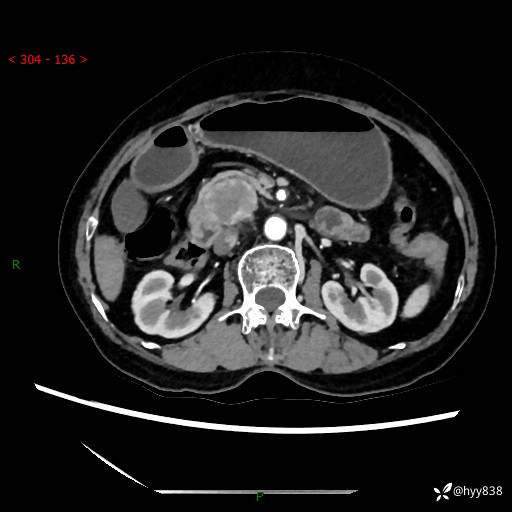

71岁/女,腹痛1月余。腹膜后肿物,间质瘤 VS 副节瘤 VS 平滑肌肉瘤---(有结果)

【患者信息】:71岁/女

【主诉】:腹痛1月余

【现病史及既往史】:患者于1月前无明显诱因出现右下腹部疼痛不适,呈阵发性隐痛,尚可耐受,放射至后背部及腰部疼痛,伴排便困难,不伴其它部位疼痛,无嗳气,无不洁饮食,无黑便,无恶心、呕吐、腹胀腹泻、呕血、发热、寒颤、厌油、黄疸,多次就诊于当地区太湖医院拍片示: 行抗炎等对症支持治疗,效果尚可。现患者上述不适症状明显进一步加重,为求进一步治疗遂来我院门诊就诊,门诊以“十二指肠肿瘤?”收住我科。 起病以来,精神、睡眠可,食欲可,大便异常、小便正常,体力、体重无明显下降。

【检查】:腹部CT增强扫描(外院CT平扫)